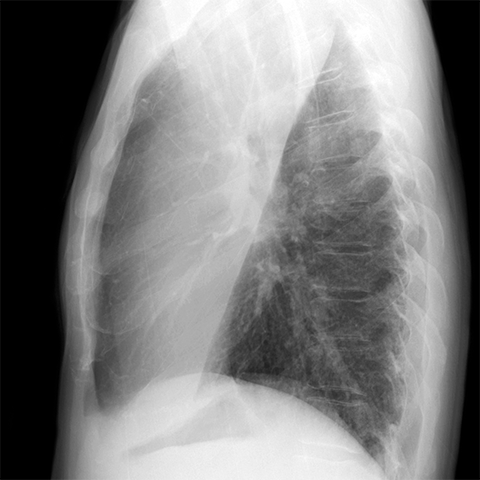

Left Upper Lobe Pneumonia [2 of 2]